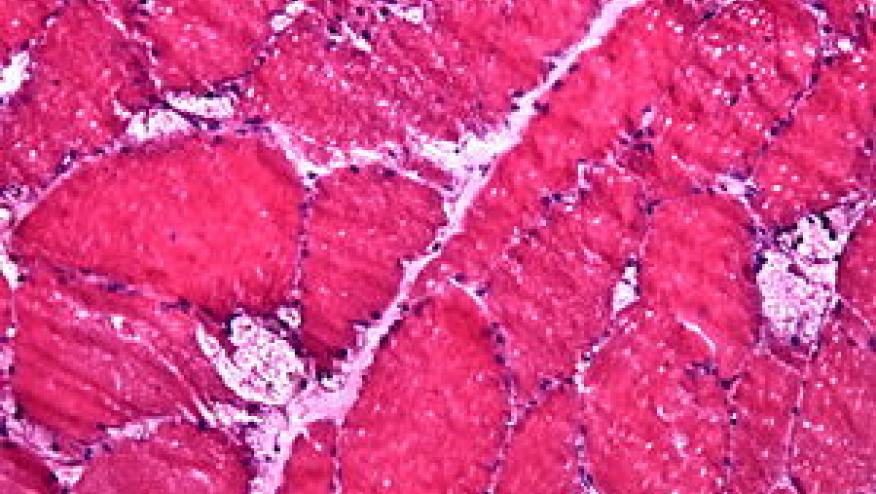

Pompe disease (also called glycogen storage disease type II) is an autosomal recessive disease, caused by a deficiency of the lysosomal acid alpha-glucosidase enzyme, with resultant accumulation of glycogen in the lysosome causing damages to muscle and nerve cells. One subtype has an infantile onset (before 2 years of age) and often manifests as infantile weakness, hypotonia, heart failure, and early death. Those with later onset disease have less cardiac disease and more prominent skeletal involvement and lower limb weakness and has an overall slower progression and better prognosis than infantile onset disease.